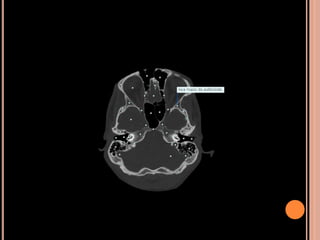

CALCIFICAÇÕES NÃO NEOPLÁSICAS DO PLEXO

CORIÓIDE

VL, assimétrica ou unilateral;

Usualmente não apresenta crescimento em exames

seriados;

TC